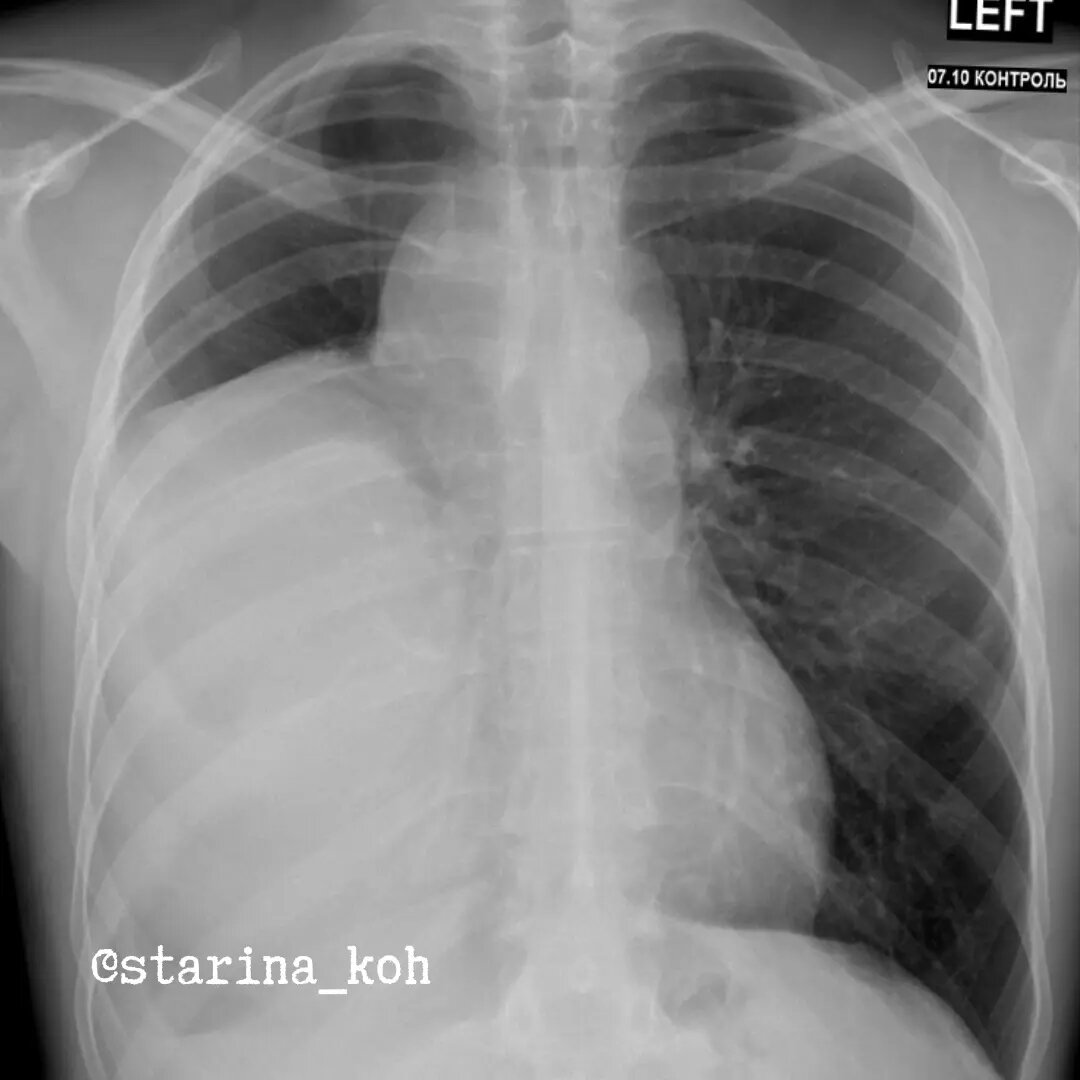

Маленький пост об очень большой опухоли

Мы привыкли, что любое упоминание о злокачественном процессе в грудной клетке ассоциируется у нас исключительно с раком - опухоли из эпителия бронхов/бронхиол. Редко, но бывают исключения. Как например, у этого молодого человека 36 лет - более чем за полгода до госпитализации по поводу ОРВИ была выполнена ФЛГ - в правом лёгочном поле найдено обширное затемнение (образование? гидроторакс?).

До момента проведения ФЛГ пациента ничего особенно не беспокоило - периодический сухой кашель и неприятные ощущения в грудной клетке. Чуть позже выполнил КТ, где выявилось образование средостения. Через полгода после консультации онколога была выполнена повторная КТ ОГК, ОБП - где отмечалась отрицательная динамика по размерам опухоли, а подозрительные отдаленные очаги выявлены не были.

Лабораторные показатели также были в норме. Без больших трудностей (согласитесь, в такую большую опухоль попасть несложно) выполнена трансторакальная биопсия - липосаркома миксоидного типа. Как можно было понять еще при КТ, что мы имеем дело со злокачественным процессом, один из компонентов которых - жировая ткань?

Традиционный симптом (и не только в грудной клетке) - симптом "грязного жира" - неоднородной, "вуалеобразной" плотности клетчатки, без данных за предшествующую травму. У пациента он особенно был выражен в нижних отделах плеврального компонента - см. изображение. Естественно, для удаления подобного образования потребовалась операция - проведена стернотомия с торакотомией - почти всю плевральную полость справа занимает плотная массивная опухоль, которая распространяется из переднего средостения, общими размерами 40 х 30 см, при этом справа дифференцировалась только верхняя доля (остальные - коллабированы). Опухоль не врастала в легкое, плевру и перикард, однако медиастинальный компонент был неотделимо связан с плечеголовной веной (перевязана и удалена), вместе с опухолевым конгломератом был удален правый диафрагмальный нерв. Произведена лимфодиссекция, операция окончена сеансом фотодинамической терапии. На последнем слайде - вы можете видеть рентгенограмму после операции.